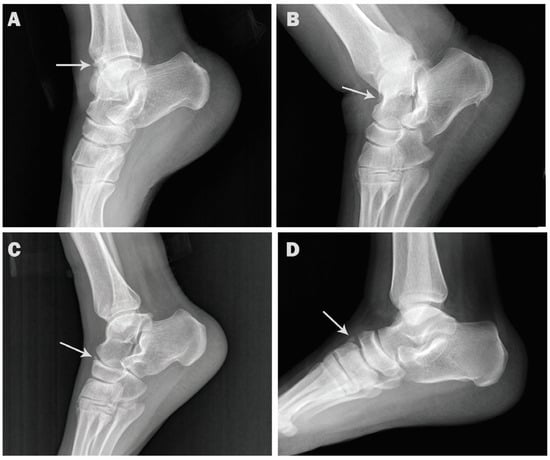

| Os trigonum | 154 (15.4) | 65 (13.0) | 89 (17.8) | 105 (15.6) | 49 (15.0) |

| p value | 0.0436 * | 0.8522 ns | |||

| Os calcaneus secundarius | 3 (0.3) | 2 (0.4) | 1 (0.2) | 2 (0.3) | 1 (0.3) |

| p value | 1.000 ns | 1.000 ns | |||

| Os supratalare | 3 (0.3) | 2 (0.4) | 1 (0.2) | 1 (0.1) | 2 (0.6) |

| p value | 1.000 ns | 0.2493 ns | |||

| Os subfibulare | 6 (0.6) | 2 (0.4) | 4 (0.8) | 3 (0.4) | 3 (0.9) |

| p value | 0.6866 ns | 0.3979 ns | |||